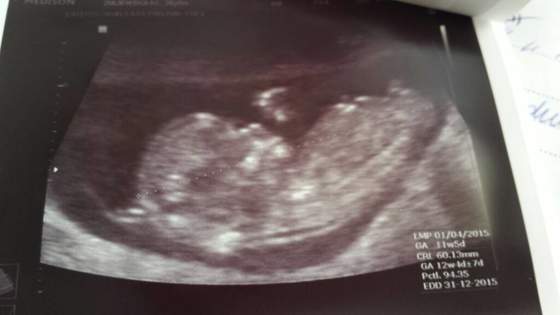

ImageUploadedByForum BabyBoom1434993087.513071.jpg

• ImageUploadedByForum BabyBoom1434993087.513071.jpg

21,7 KB · Wyświetleń: 92